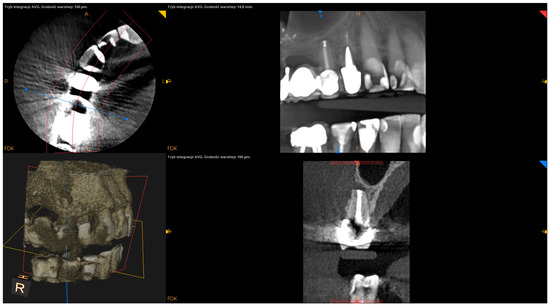

- The status of radiographic healing (rated in all sections, according to modified PENN 3D criteria [28]) was classified as complete healing (Figure 1), incomplete healing (Figure 2), uncertain healing (Figure 3), or unsatisfactory healing (Figure 4).

Figure 3. CBCT image (CS 8100 3D Carestream Dentalⓡ) example of uncertain healing based on PENN 3D criteria. Non-English annotations present software technicalities (AVG integration mode and layer thickness).

Figure 4. CBCT image (CS 8100 3D Carestream Dentalⓡ) example of unsatisfactory healing based on PENN 3D criteria. Non-English annotations present software technicalities (AVG integration mode and layer thickness).